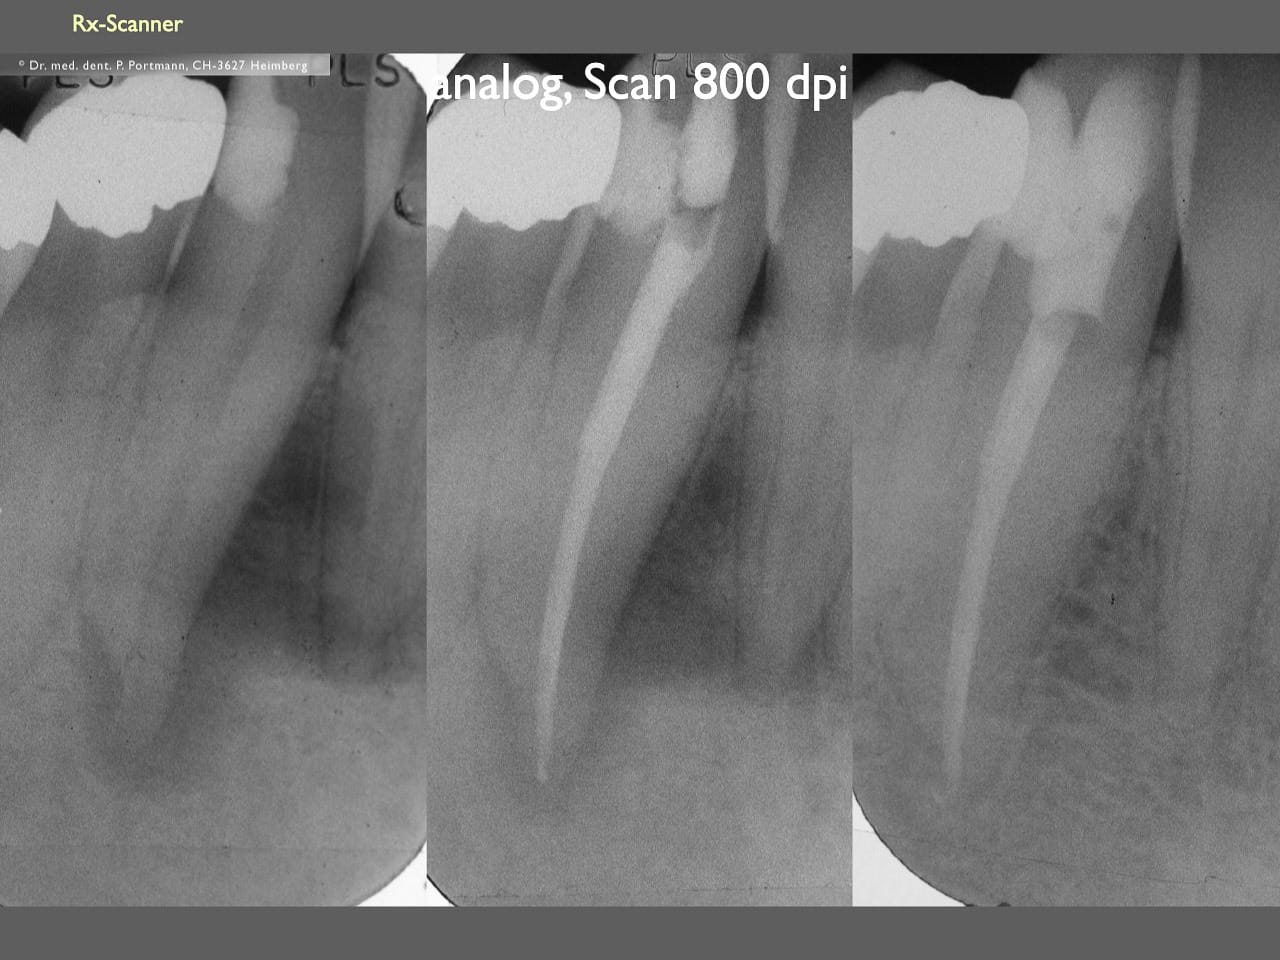

dental Scannen in der Zahnarztpraxis. Study Club vom 28.2.2010. Von peter portmann, Veröffentlicht am 28. Feb. 2010 — 3 min Lesezeit dokumentationfoto Auf dieser Seite Zahnarztpraxis-Trilogie zu Fotografie und Dokumentation Portrait Fotografie Scannen Scannen